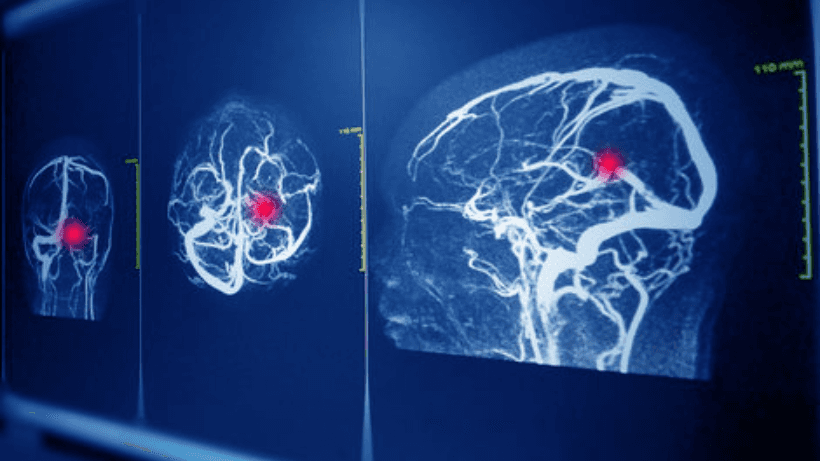

A. Mga Pagsusuri sa Imaging: Ito ay tulad ng mga tool ng detektib na ginagamit ng mga doktor upang makita kung ano ang nangyayari sa loob ng iyong utak.

- MRI: Ito ay isa pang paraan ng imaging gumagamit ng mga magnet at alon ng radyo upang lumikha ng detalyadong mga imahe ng utak. Ito ay lalong mahusay sa pagpapakita ng mas maliliit na aneurysm.

- Cerebral Angiography: Isipin ito bilang isang mapa ng daan ng iyong mga daluyan ng dugo. Ang isang espesyal na pangulay ay na-injected sa iyong daloy ng dugo, at ang mga x-ray ay dadalhin upang matukoy ang anumang mga aneurysms.